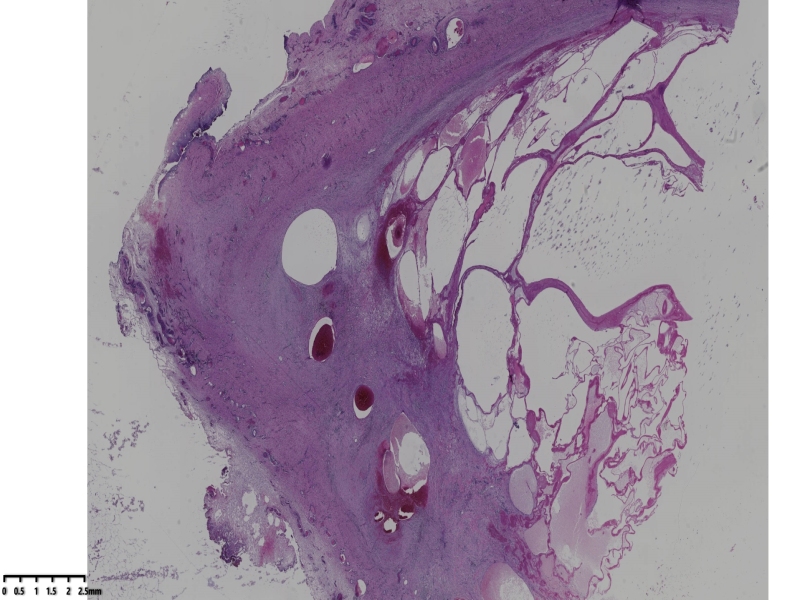

男、75岁。

这是一个腺瘤样瘤,特殊的地方在于切面呈蜂窝状,

镜下可见瘤细胞胞浆丰富,可见泡沫,部分瘤细胞呈印戒样,纤维组织间隔,瘤组织中央血管增生扩张,组织梗死。